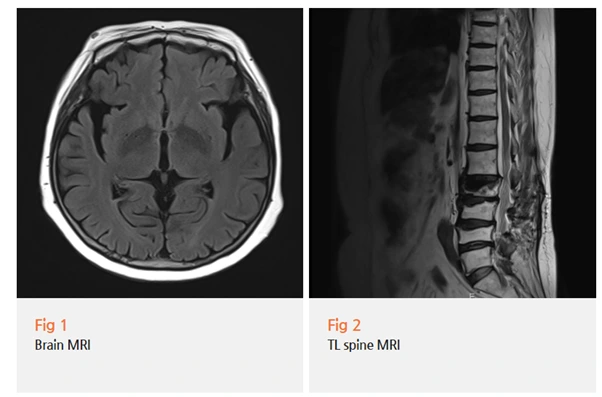

저한테로 협진하러 온 환자분의 상태를 확인하고,

추가로 뇌 MRI 및 세밀한 신경학적 검사를 진행했어요.

타 병원에서 받으셨던 검사들도 다시 꼼꼼히 살펴봤고요.

결과는 파킨슨병이었습니다.

사실 파킨슨병은 영상 검사만으로는 진단이 어려운 질환입니다.

CT나 MRI로는 뇌의 구조적 변화는 볼 수 있지만,

도파민 신경세포의 기능 저하는 직접 확인하기 어렵거든요.

그래서 파킨슨병 진단은 영상 검사보다는

신경학적 검사가 더 중요해요.